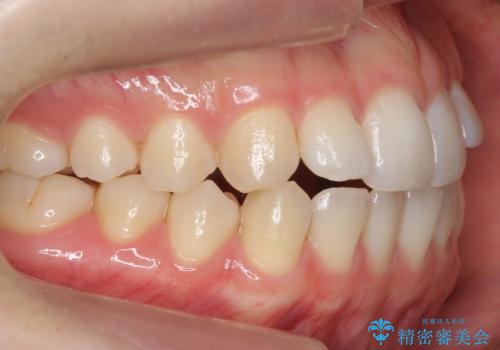

咬んでも前歯が閉じない 矯正治療で見た目を含めて改善

咬んでも向こう側が見える、前歯が閉じない症状でした。また、上の前歯が少し前に出ている状態でした。

上の前歯をわずかに削る処置を行い、後ろに下げながら下の歯となるべく咬むように矯正治療を行いました。